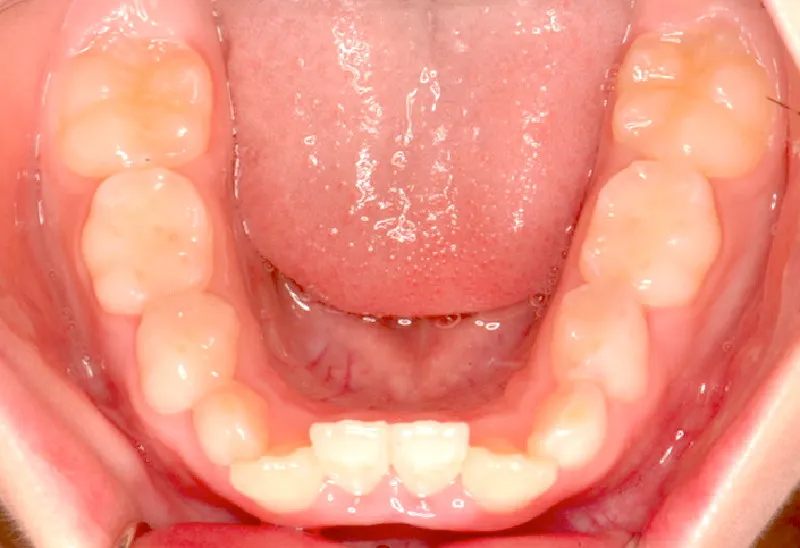

永久歯に生え変わってからはマルチブラケット装置を使用し、噛み合わせ・見た目をしっかり仕上げました。

治療回数42回、4年6ヶ月の治療期間で矯正治療を終了しました。

治療終了後